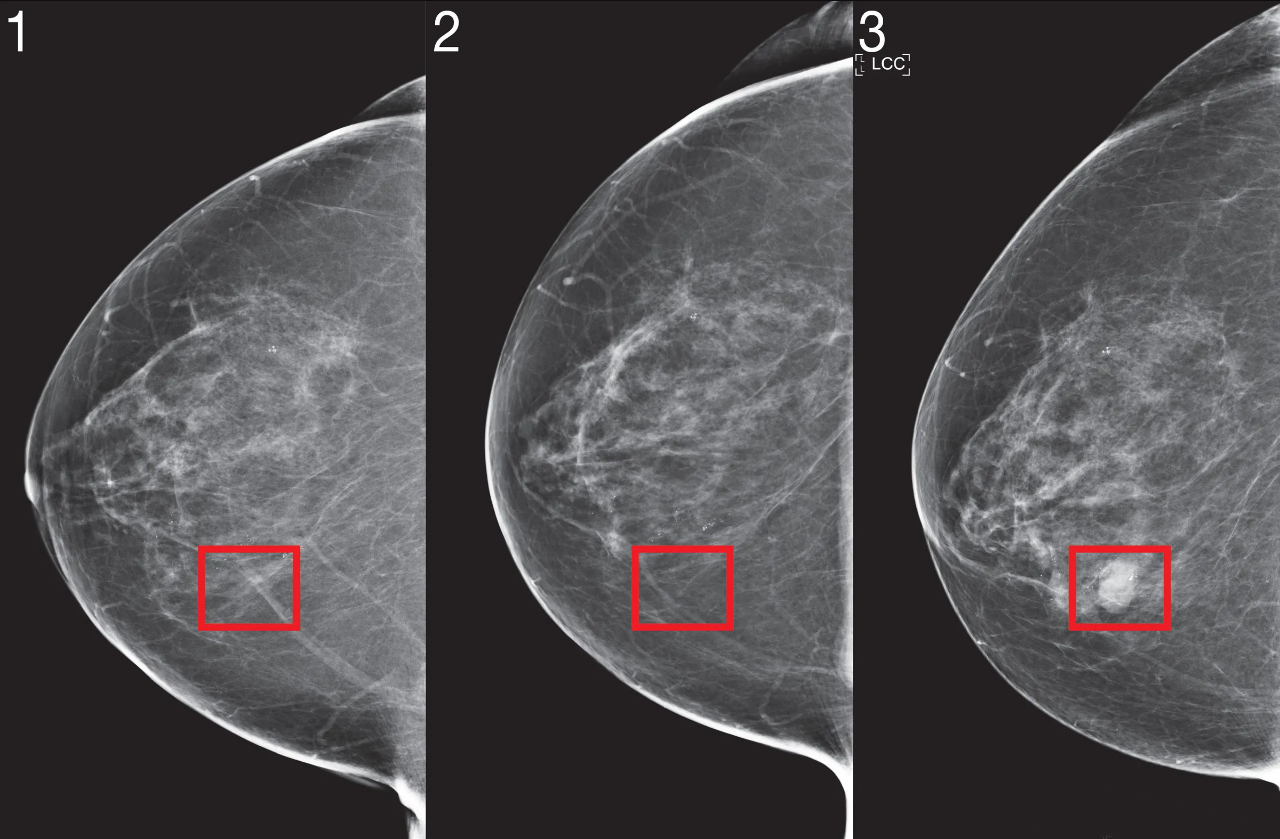

Cách phát hiện ung thư vú: Những phương pháp quan trọng giúp phát hiện

Ung thư vú là một trong những loại ung thư phổ biến nhất ở phụ nữ. Tuy nhiên, nếu phát hiện sớm, tỷ lệ điều trị thành công rất cao. Việc phát...